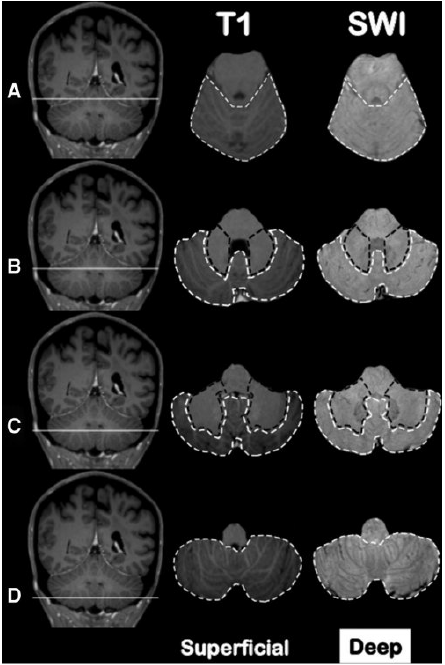

Classificazione Topografica dei Micro-sanguinamenti

Per testare l’ipotesi dello studio, è stato sviluppato un sistema di classificazione topografica dettagliato dei CMB cerebellari, basato su immagini MRI ad alta risoluzione. Il cervelletto è stato suddiviso in due regioni principali:

- Regione superficiale: include la corteccia cerebellare e il verme.

- Regione profonda: include i nuclei grigi profondi del cervelletto e la sostanza bianca circostante.

Sulla base di questa suddivisione, sono stati definiti tre pattern di distribuzione esclusivi per i CMB:

- Strettamente superficiale: CMB presenti solo nella corteccia cerebellare e/o nel verme.

- Strettamente profondo: CMB presenti solo nei nuclei profondi e/o nella sostanza bianca.

- Misto: CMB presenti simultaneamente sia nelle regioni superficiali che in quelle profonde.